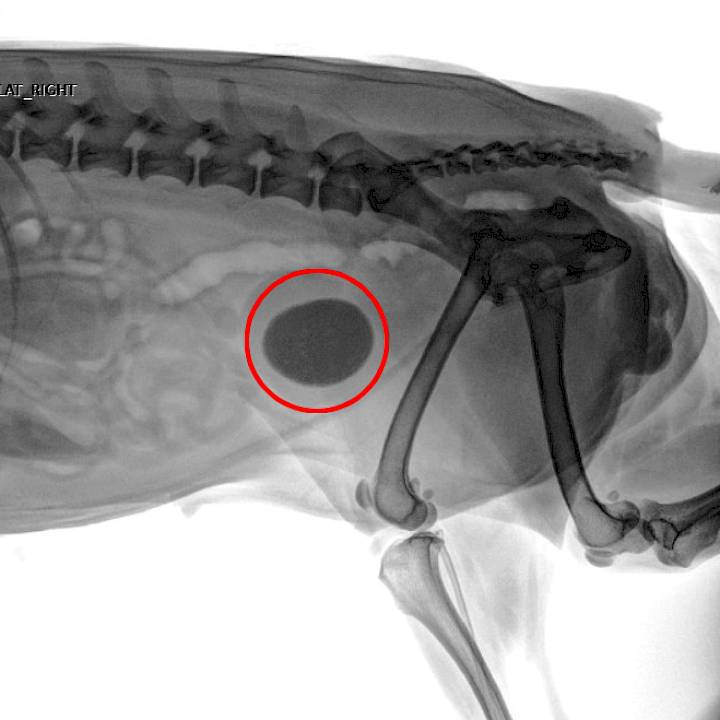

ลาเต้เป็นสุนัขเพศเมียที่เป็นมิตร และกำลังป่วยด้วยอาการปัสสาวะเป็นเลือด ทำให้เรารู้ว่ามีบางอย่างร้ายแรงเกิดขึ้น ทีมสัตวแพทย์ได้ตรวจอย่างละเอียดพบว่าลาเต้มีก้อนนิ่วขนาดใหญ่อยู่ในกระเพาะปัสสาวะ และทำให้เธอต้องขับถ่ายอย่างยากลำบาก

ทีมศัลยแพทย์ผู้มีประสบการณ์ของเราได้ผ่าตัดเอาก้อนนิ่วนั้นออกไป ตอนนี้ลาเต้หายเป็นปกติดีแล้วและกลับคืนสู่ชุมชนของเธออย่างมีความสุขแล้ว